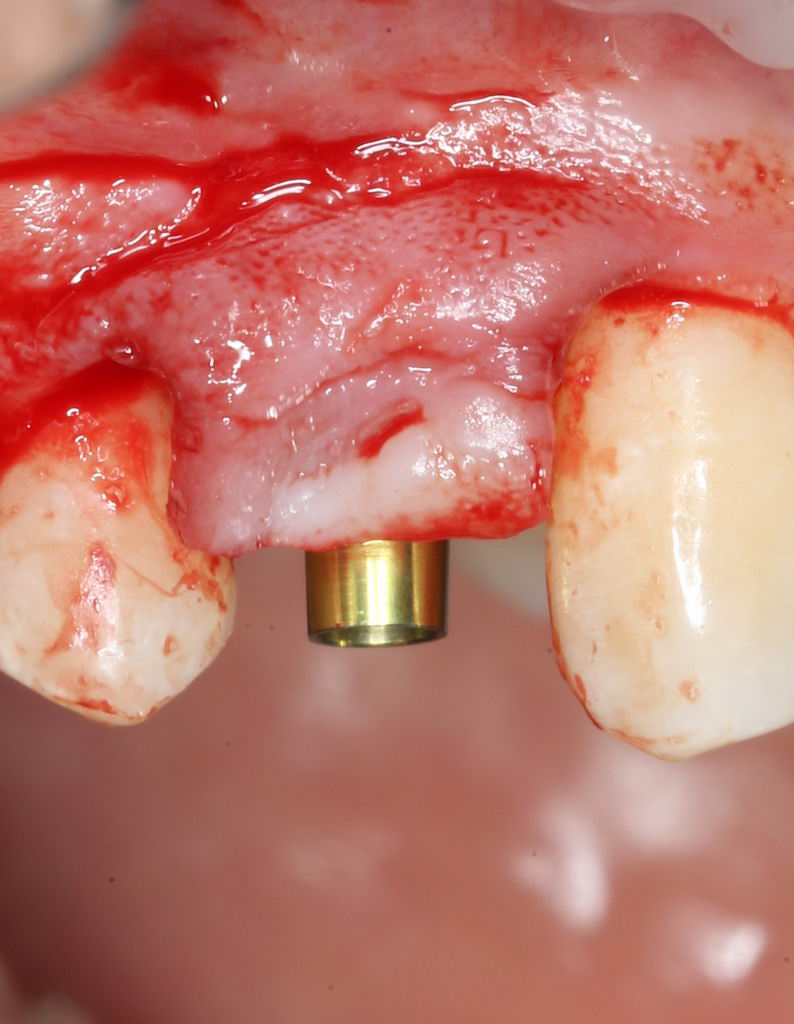

Установка формирователя десны.

Одномоментная установка формирователя десны позволяет сократить время и удешевить лечение — ведь по мере интеграции имплантата мы получаем нормально сформированный контур десны, готовый к установке протетической конструкции. Но это возможно лишь тогда, когда с объемами мягких тканей в области имплантата всё в порядке. То есть, как раз в нашем случае.

В CLINIC IN используют только одноразовые формирователи и только один раз:

С учётом клинических условий, мы подобрали к установленному имплантату формирователь Slim (без расширений) высотой 3 мм:

Для окончательного формирования десневого контура, осталось только наложить швы.